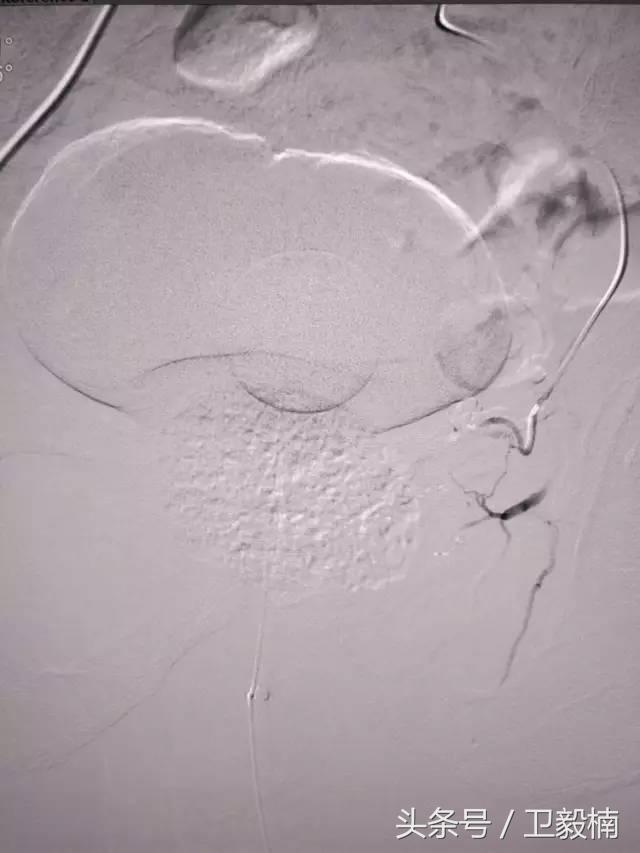

2、经导管血管栓塞法(Transcatheter embolization)

经原血管造影的导管或特制的导管,将栓塞物送至靶血管内,一是治疗内出血如外伤性脏器出血、溃疡病、肿瘤或原因未明的脏器出血。另一是用栓塞法治疗肿瘤,因肿瘤循环部分或全部被栓塞物阻断,以达控制肿瘤之生长,或作为手术切除的一种治疗手段;亦可用于非手术脏器切除,例如注射栓塞物质于脾动脉分支内,即部分性脾栓塞,以治疗脾功亢进,同时不影响脾脏的免疫功能。

常用的栓塞物质如自体血凝块、明胶海绵、无水酒精、聚乙烯醇、液体硅酮、不锈钢圈、金属或塑料小球及中药白芨等。